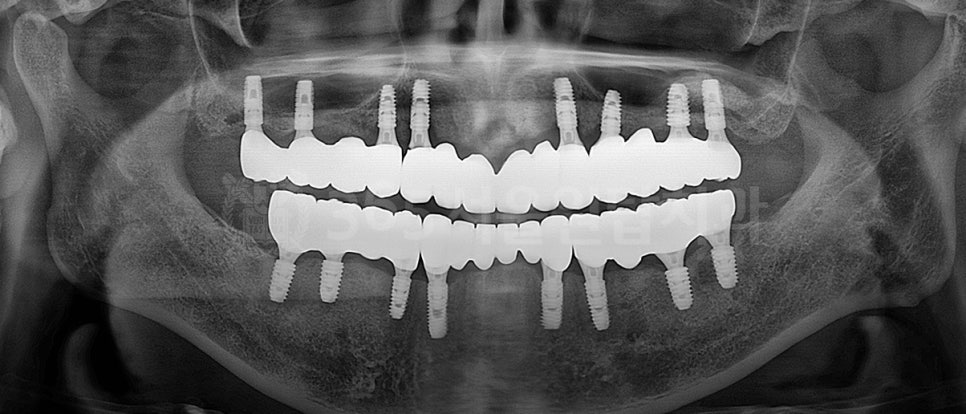

파노라마와 3D CT로 뼈 상태와

신경 위치를 정확히 확인하고,

불필요한 절개를 줄이는 방향으로

수술 계획을 세웁니다.

파노라마 엑스레이 설명을 위한 예시자료입니다.

계획이 정확해질수록

통증과 수술 시간은 줄어듭니다.